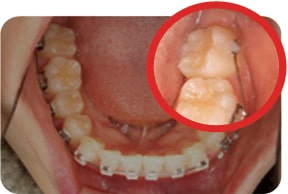

Case 1

2017. 07. 28

2017. 12. 05

2018. 03. 20

2018. 04. 28